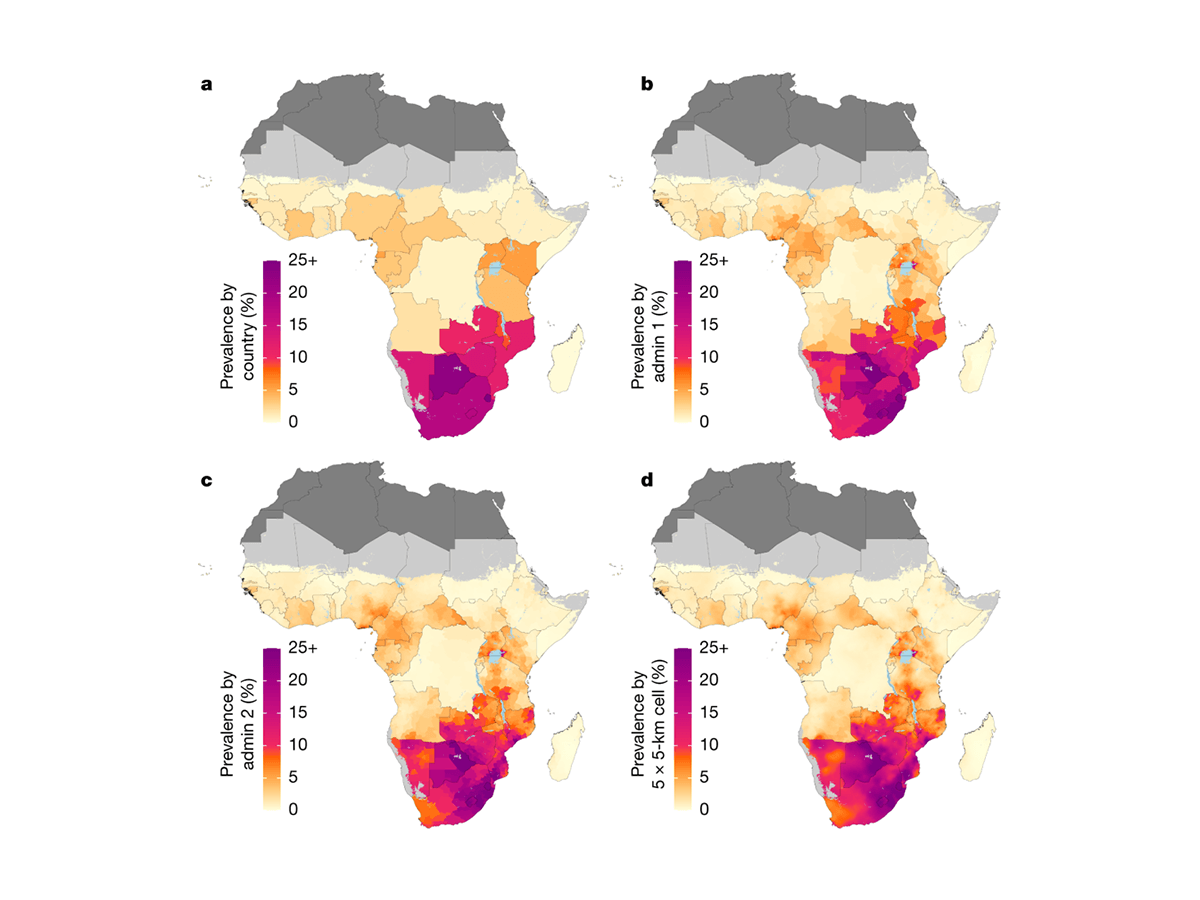

Icap Research Contributes To Detailed Maps Of The Hiv - Source

Maps Of The Research Location Morphoconservation Means - Source